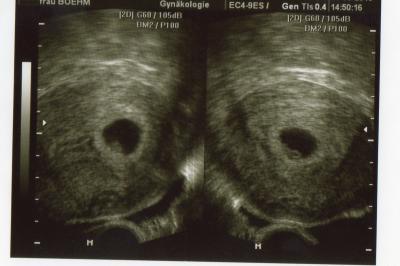

US Bilder 6+0 und 8+0

Hallo, ich versuche mal die Bilder einzustellen, vielleicht klappts... LG hier 6+0